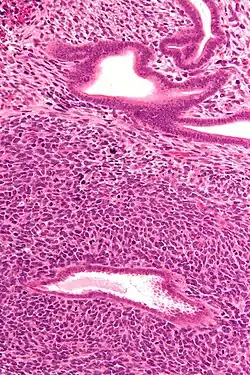

| Micrograph of a uterine adenosarcoma showing a mitotically active malignant stroma and benign glands. H&E stain. | |

Uterine adenosarcoma is an uncommon form of cancer that arises from mesenchymal tissue of the uterus and has a benign glandular component.

Uterine adenosarcoma have, by definition, a malignant stroma and benign glandular elements. The World Health Organization (WHO) criteria have a mitotic rate cut point; however, this is often disregarded, as bland-appearing tumours with a low mitotic rate are known to metastasize occasionally.[2]